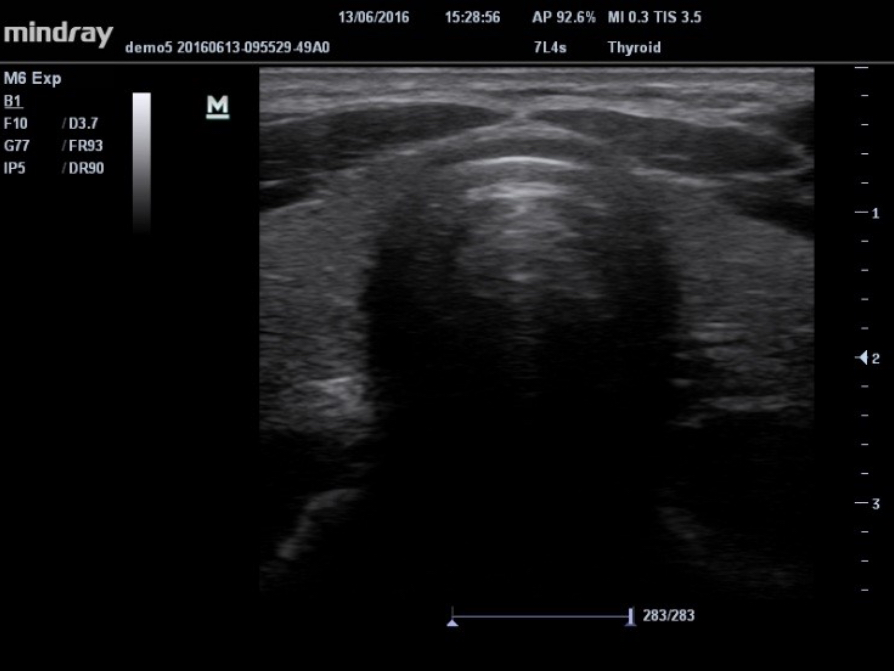

HR Flow?

?????? ???? ???? ????? ???? ??? ? ??? ?? ??? ?? ??? ???? ? ?? ???? ?????.

UWN ?? ??(???? ???)

UWN ?? ??? ?? M6? 2? ??? ? ??? ?? ??? ?? ???? ???? ?? ??? ??? ??? ? ????.

- ?? ??? ??? ??, ??? ??? ???

- ?? MI ??? ?? ??? ?? ?? ??

IMT(Intima-Media Thickness)

?? ? ?? ? ?? ? ??? ?? ???? ??? ???? ??? ?????.